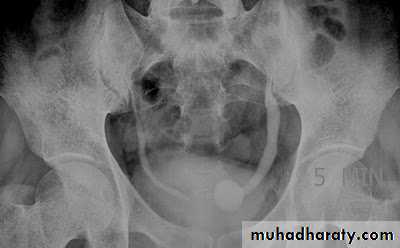

Ureterocele :

Congenital cystic dilatation of lower end of ureter ( intra-mural part) due to pin-hole meatus . May be simple or ectopic .

simple : the orifice is in proper position of bladder ,

Ectopic >> in bladder neck , urethra , uterus & vagina .

IVU :

- There is rounded or elliptical dilatation of lower end of ureter with thin lineal filling defect around it , resembling (cobra head appearance),

- Proximal dilatation of rest of ureter .

- In advanced cases hydronephrosis .

- In obstructed ureterocele , filling defect in the bladder